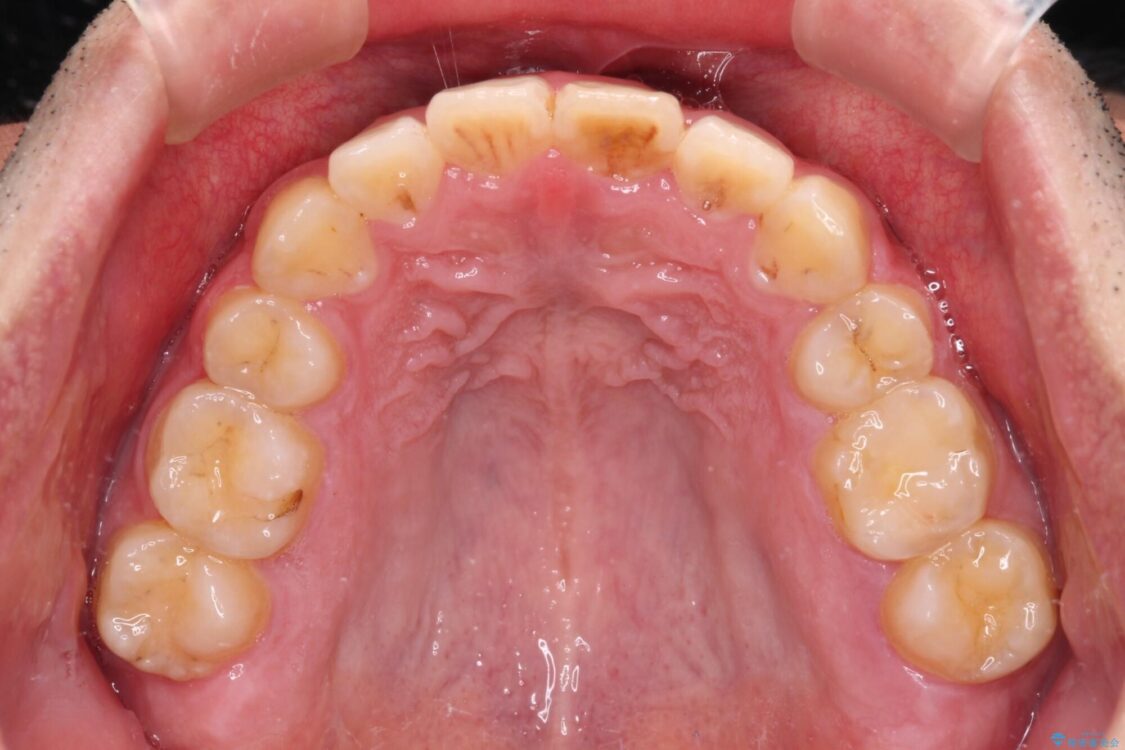

高校時代に行った抜歯矯正が後戻りをしたとのことで来院された患者様です。

再矯正であることから、目立ちにくい装置を希望されたため、インビザラインにて矯正治療を行うこととしました。

下顎骨が左側に変位しているため、正中が合わないことは予想できましたが、歯列が整った後も咬み合わせが安定せず、咬み合わせを落ち着かせるために1年以上の期間を要しました。

治療前

• 後戻りでデコボコの前歯 インビザライン矯正治療 治療前画像